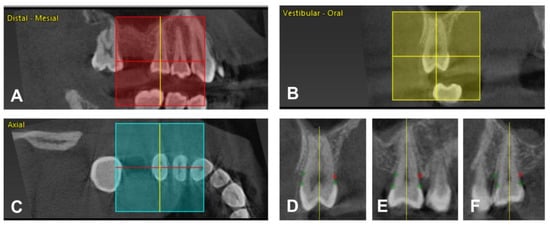

- Fleiner, J.; Hannig, C.; Schulze, D.; Stricker, A.; Jacobs, R. Digital method for quantification of circumferential periodontal bone level using cone beam CT. Clin. Oral Investig. 2013, 17, 389–396. [Google Scholar] [CrossRef]